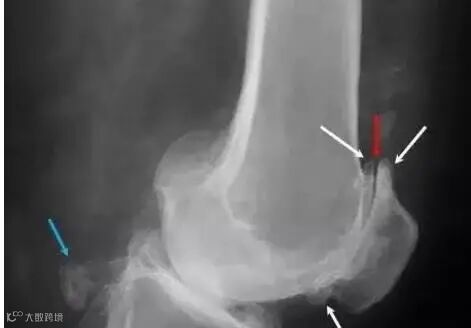

比如说,膝关节骨质增生,是因为膝关节骨性关节炎(Osteoarthritis)或膝关节外伤后的创伤性关节炎(Traumatic arthritis)导致关节病变、损伤以后,关节为了建立新的稳定,继发出现了骨质增生。